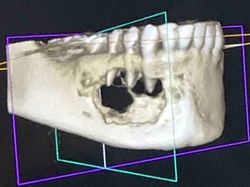

Kondisi Tubuh Manusia Ini Bikin Takjub dan Merinding